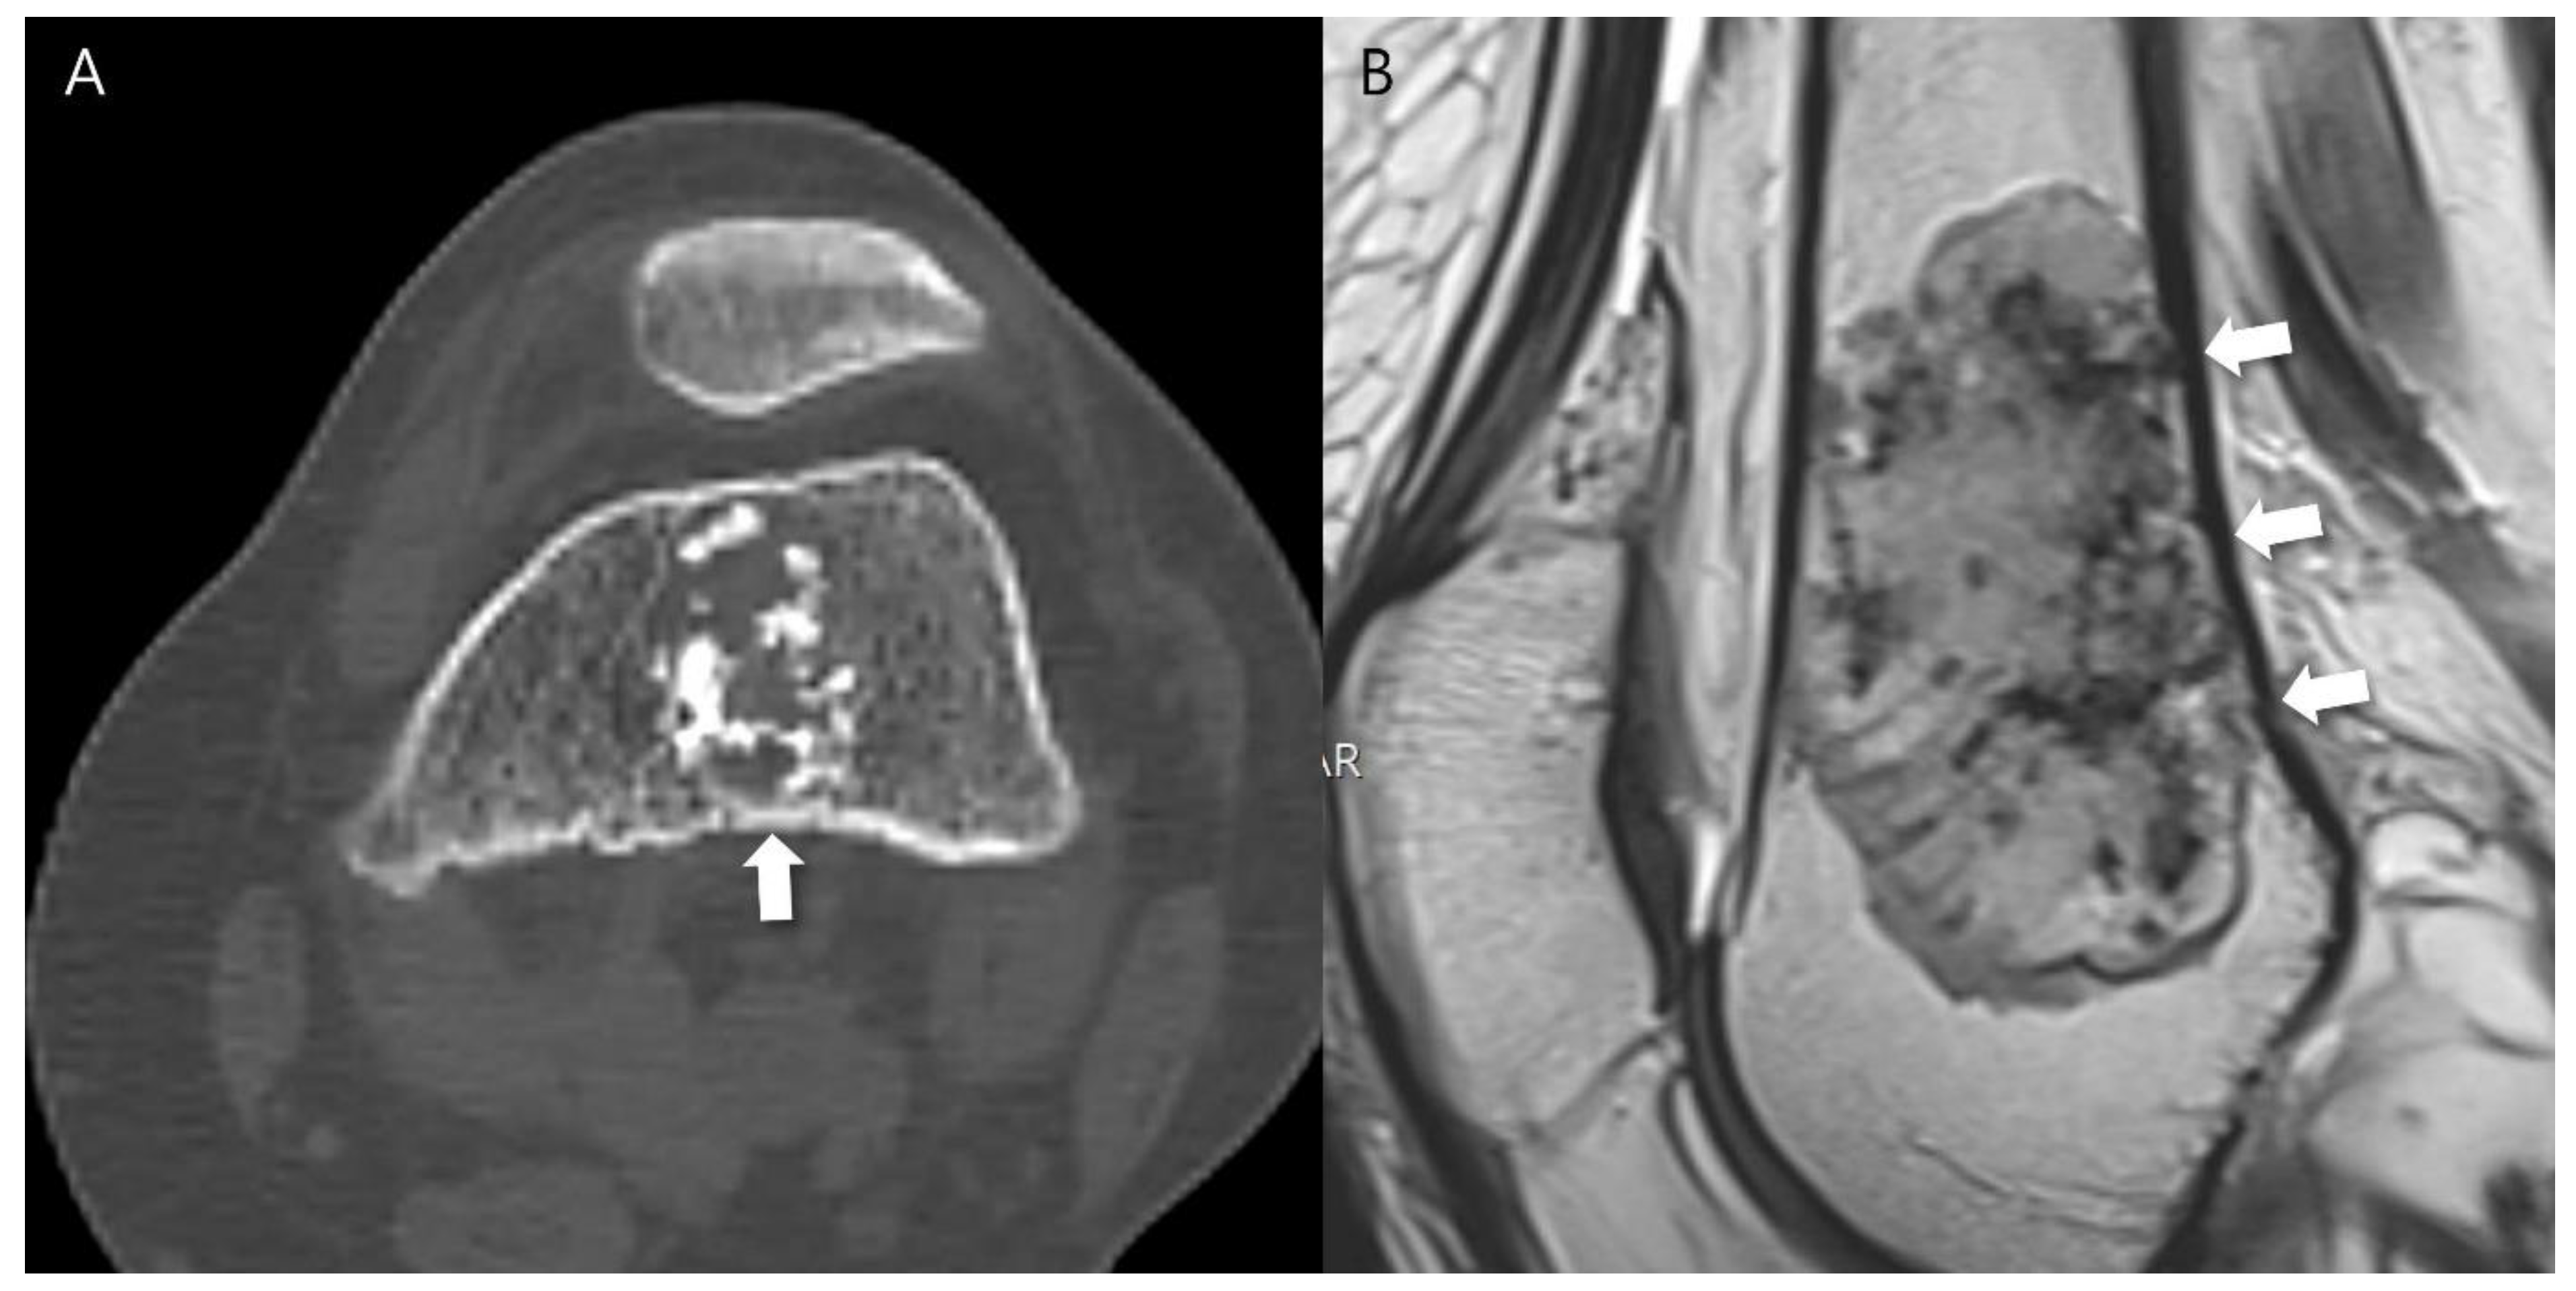

Any aggressive CT features for the grading of central cartilaginous bone tumors including (i) deep endosteal scalloping ≥ 2/3 of the normal cortical thickness (Figure 1), (ii) extensive endosteal scalloping ≥ 2/3 of the lesion length (Figure 2), (iii) expansile cortical remodeling (Figure 3), and (iv) cortical destruction with or without soft tissue extension (Figure 4) were also evaluated. The CT images were evaluated in conjunction with the plain radiographs and/or MRI. After finishing the independent review, a consensus review of the CT was performed. The two radiologists reviewed the CT images together to reach a final consensus on discrepant interpretations from the independent reading.

Figure 4. Cortical destruction with small extraosseous soft tissue extension in a patient with CS2 in the scapula. (A) An axial CT image shows a lobulated mass containing chondroid matrix mineralization and focal cortical destruction (arrow). (B) An axial T1-weighted fat-suppressed enhanced MRI shows a lobulated mass with extraosseous soft tissue extension (arrowhead).